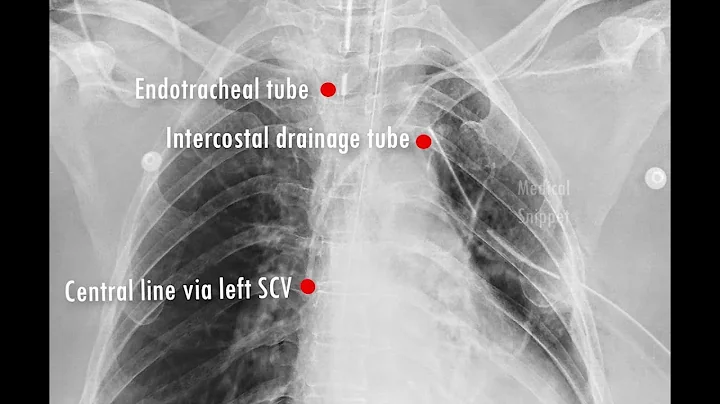

Beginners Guide To Lines And Tubes - How To Read A Chest Xray